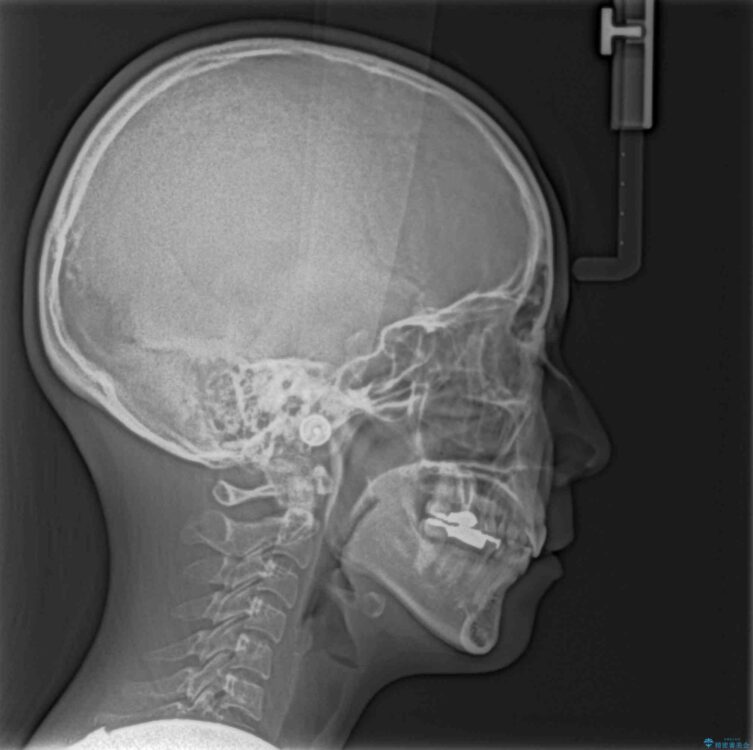

治療前

• デコボコと口元の突出感 ハーフリンガルでの抜歯矯正 治療前画像